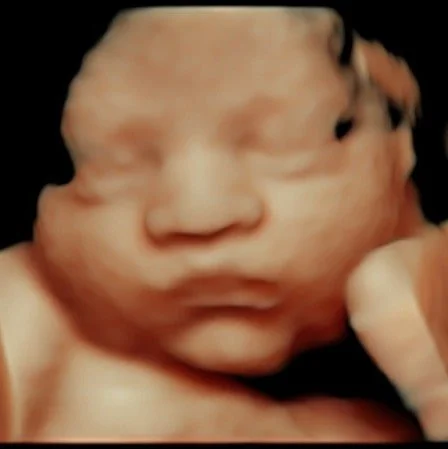

Clearer View of Baby’s Face & Features

- Shows detailed facial features

- Helps see expressions like smiling or yawning

- More natural skin-tone appearance